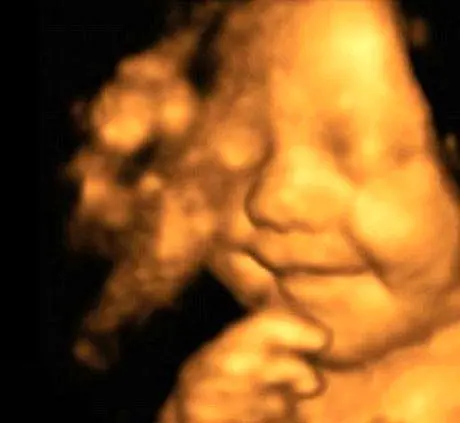

ین نوزاد بریتانیایی که “لئو” نام دارد از زمان تولدش تا کنون هیچ گاه خنده از روی صورتش محو نشده است، به همین دلیل والدینش اعتقاد دارند او شادترین نوزاد جهان است. تمامی تصاویری که از سونوگرافی هفته 31 به بعد دوران بارداری مادر لئو موجود است به نوعی این ایده را تأیید می کند، زیرا به طرز شگفت انگیزی جنین در رحم مادرش همواره لبخندی به لب داشته است.

اما به گفته مادرش این سونوگرافی ها تازه شروع ماجرای عجیب و دوست داشتنی و لئو است، این نوزاد پس از تولد همیشه و همه حال حتی در زمان خواب خنده بر لب دارد. با گذشت پنج ماه از تولد لئو، نامش به عنوان شادترین نوزاد بریتانیا بر سر زبان ها افتاده و تصاویرش دست به دست شده است. این نوزاد خندان به چنان شهرتی دست پیدا کرده است که بسیاری از شرکت های آرایشی و زیبایی خواستار استفاده از تصاویر او هستند.